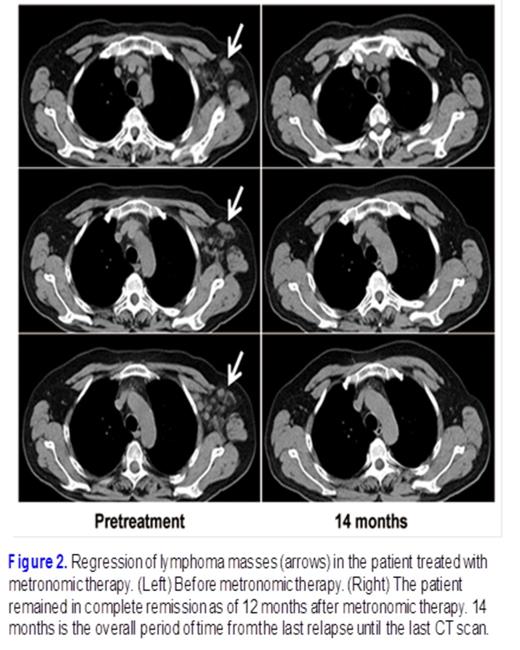

The prognosis of ALK-positive, anaplastic large cell lymphoma is usually favorable, but patients that are resistant to primary chemotherapy or who relapse early have always been associated with an aggressive clinical course and unfavorable prognosis. For a recurrent relapsing case of ALK-positive, anaplastic large cell lymphoma heavily pretreated by nearly 50 cycles of chemotherapeutic agents (Fig 1.), we developed a treatment schema of metronomically scheduled low-dose methotrexate, which successfully controlled the relapse more than 12 months (Fig. 2). The metronomic therapy that we identified from this case was an effective and economic option that caused less damage to other organs than other treatments; thus, it should be given consideration for the treatment of similar cases, especially in the setting of where the recurrence seems to be only skin disease or when other effective regimens are unavailable. Our study represents the first report of a well-documented case of ALK+ALCL which was refractory to various lines of therapy but which was subsequently successfully treated with a combination of prednisone and etoposide followed by low-dose MTX maintenance metronomic therapy.